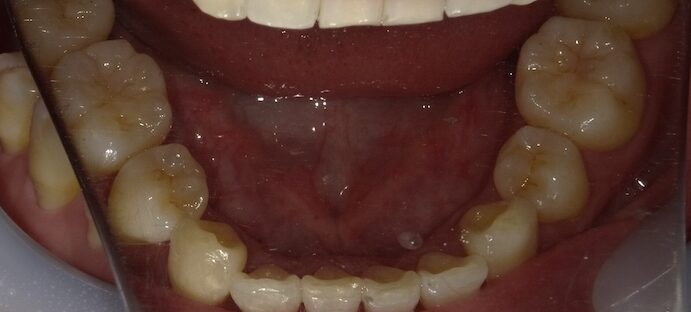

症例③:2回の矯正経験者

前歯の上下的なズレに対しワイヤー矯正で対応。

治療後は裏側ワイヤー固定+夜間リテーナーで安定。

治療方法 ワイヤー部分矯正/治療期間 8ヶ月/治療費用¥440000(税込)

治療のリスク デメリット 裏側でのワイヤー固定を長期的にする必要がある